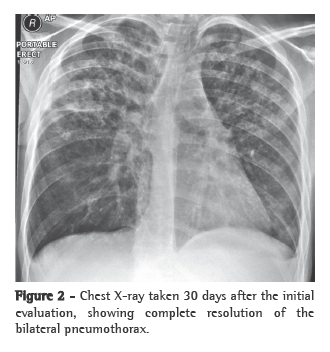

A chest X-ray revealed prominence of the medial pulmonary artery, and a computed tomography scan of the chest showed dilation of the arterial branches, with an artery-bronchus ratio of > 1, septal thickening and diffuse micronodules (Figure 1). The pulmonary function tests results showed that airflow and lung volumes were normal, but that there was a significant reduction in the diffusing capacity of the lung (30% of predicted). An echocardiogram revealed dilated right heart chambers and pulmonary artery systolic pressure estimated at 84 mmHg. The patient was submitted to the six-minute walk test (6MWT), and the distance covered was 375 m. Tests for connective tissue diseases, HIV infection, portal hypertension and chronic pulmonary embolism were all negative.

Based on the tomographic findings, we decided to investigate PVOD using bronchoscopy and bronchoalveolar lavage (BAL). The cytological analysis revealed a predominance of macrophages (89% of the total number of cells), 50% of which were hemosiderin-laden (Figure 2). Therefore, the presumptive diagnosis was PVOD.

In PVOD, the clinical profile resembles that of pulmonary hypertension resulting from other causes, including progressive dyspnea on exertion, with or without signs of cor pulmonale.(7) The diagnosis should be based on the clinical presentation and on any radiological alterations suggestive of pulmonary edema, such as septal lines, basal reticular opacities and pleural effusion.(3,5) Specifically, characteristic findings on tomography scans of the chest include smooth septal thickening, diffuse micronodules and ground-glass opacities.(8) Pulmonary function tests typically show a reduction in the diffusing capacity of the lung.(5)